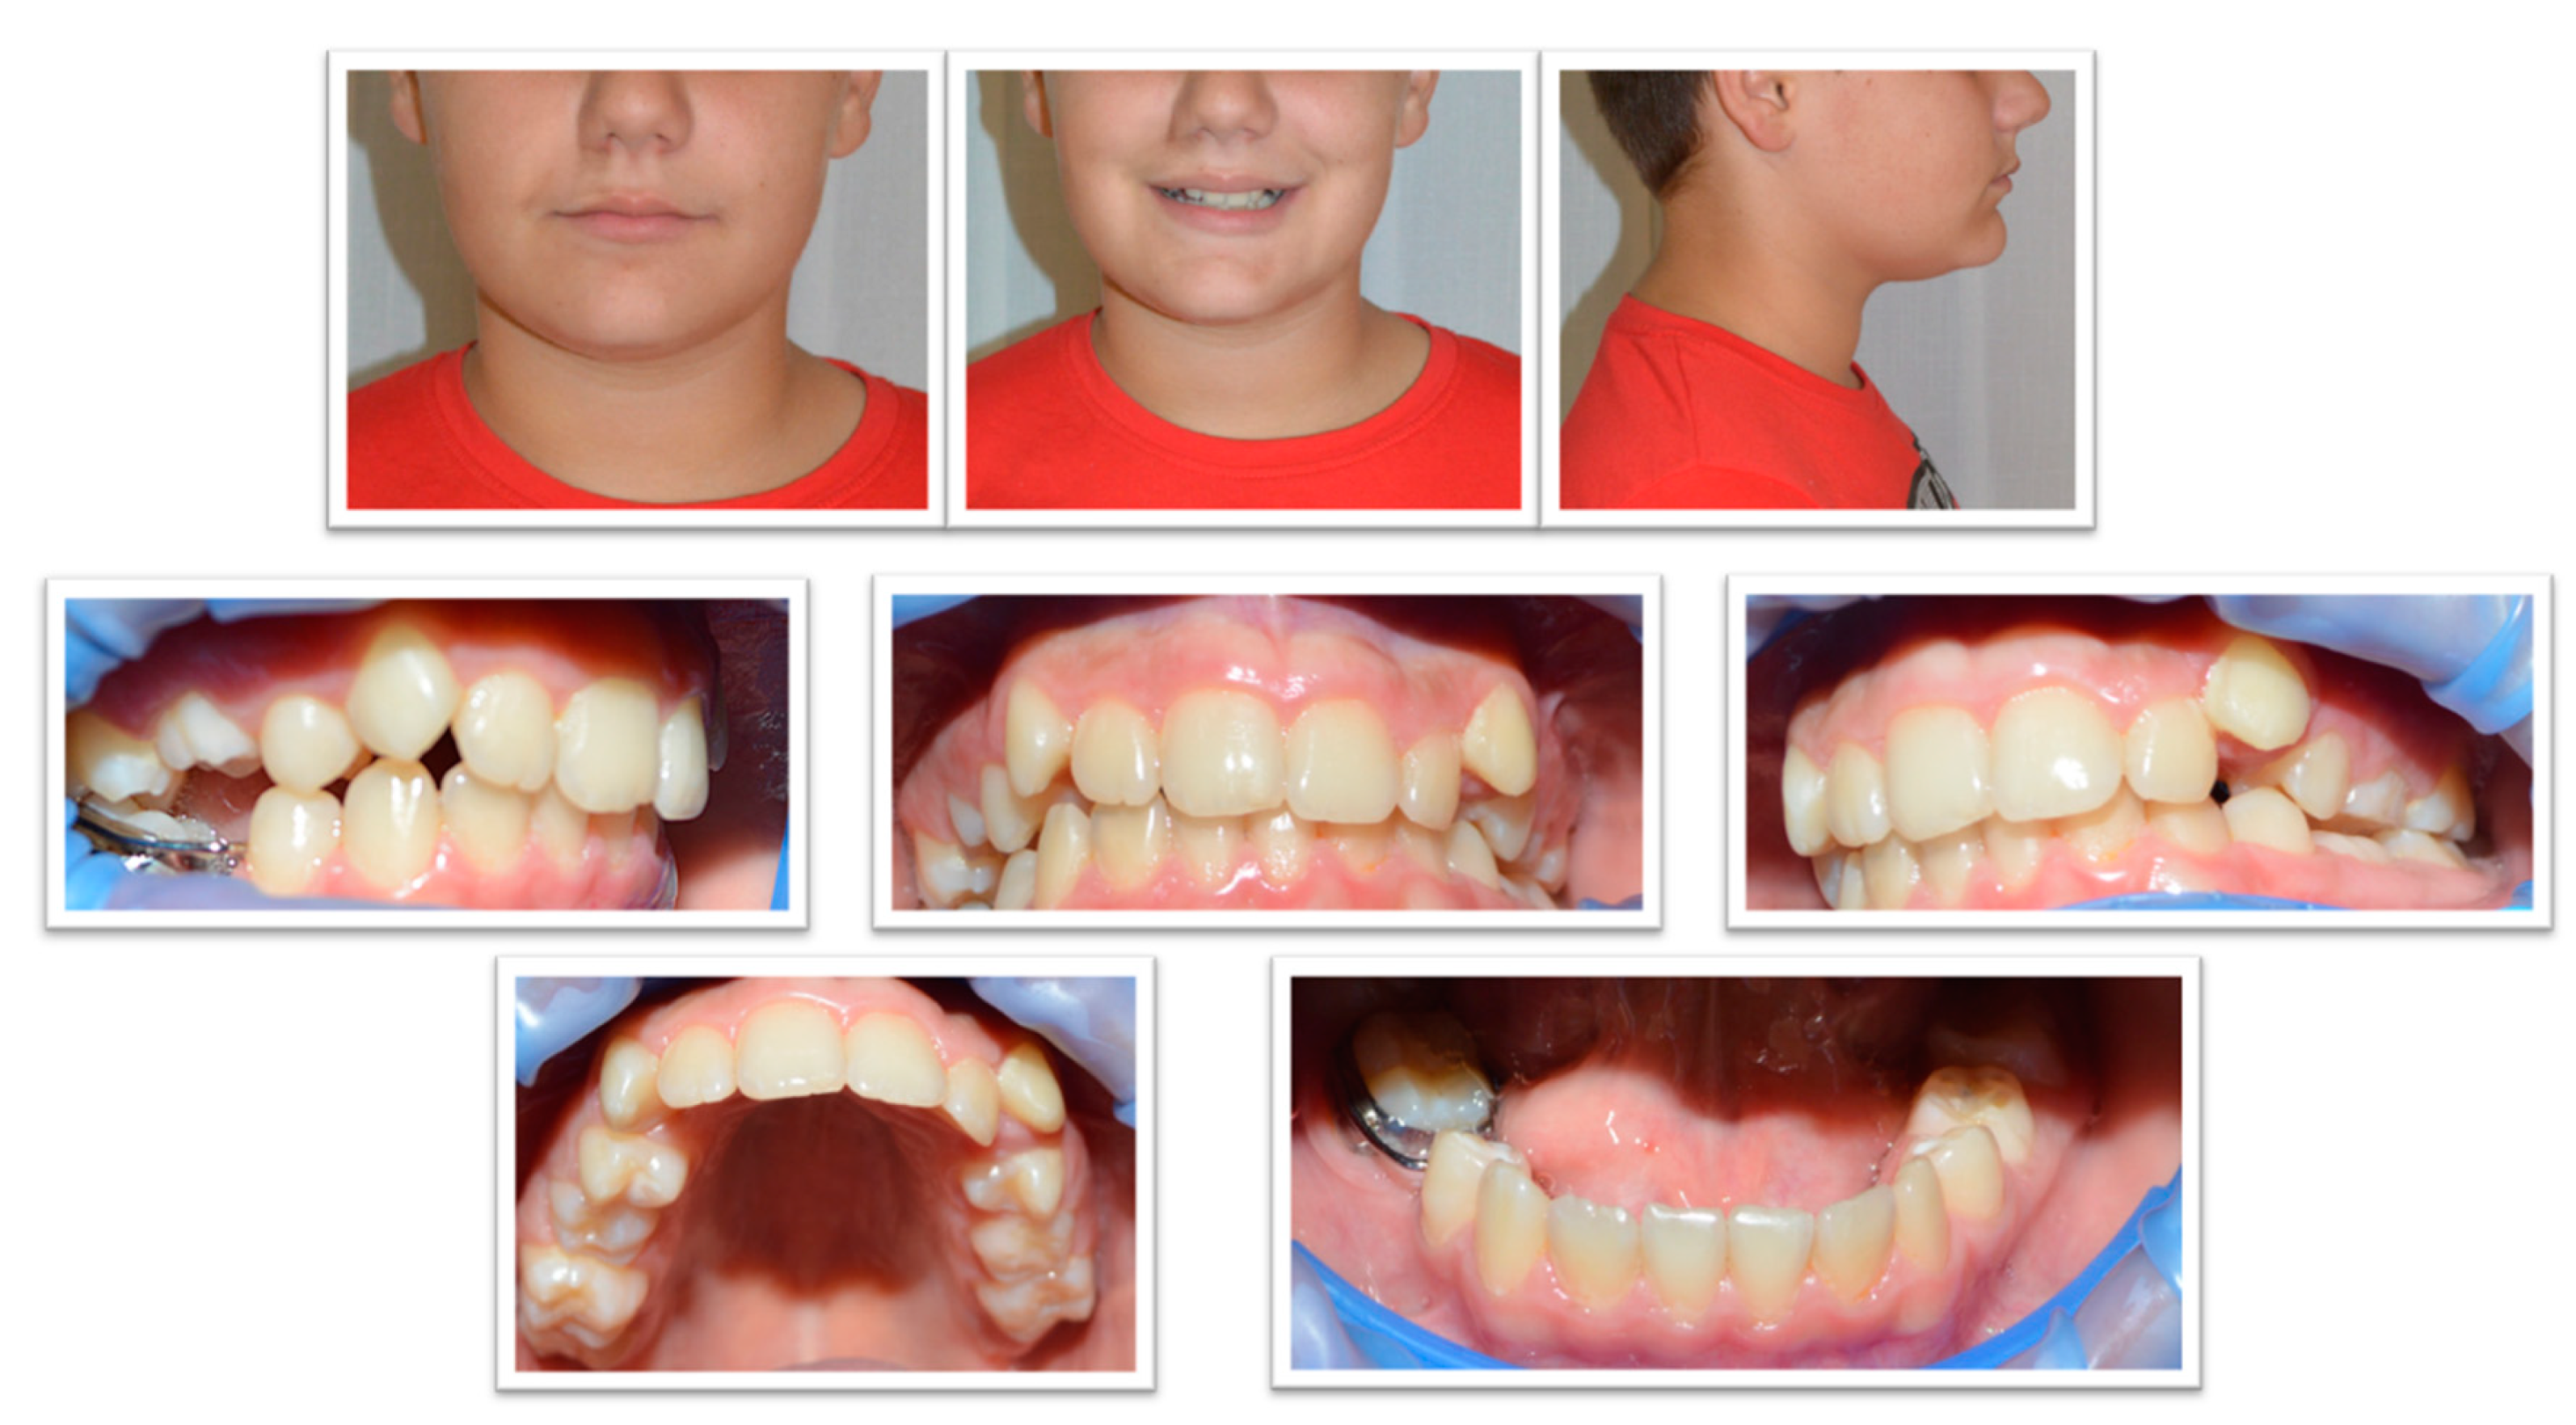

2.1. Examination, Diagnostics, and Initial Therapeutic Management